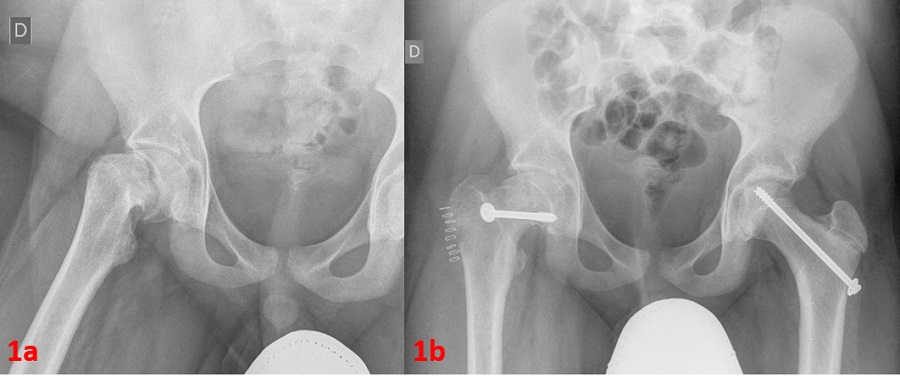

Sin embargo, acude de nuevo, por presentar empeoramiento con claudicación importante de la marcha e imposibilidad de flexoextensión derechas. A la exploración, destaca actitud de rotación externa de la cadera al realizar una flexión de esta (signo de Drehmann positivo). Se deriva nuevamente a Traumatología que realiza radiografía de cadera compatible con ECF bilateral (Fig. 1A), por lo que realizan atornillado bilateral (Fig. 1B).

Figura 1. A: radiografía anteroposterior de la cadera derecha. Se aprecia desplazamiento anterosuperior de la metáfisis proximal respecto a la epífisis. B: cambios posquirúrgicos por reducción de ECF derecho con material de osteosíntesis (tornillos)

En la actualidad, el paciente tiene buena respuesta al tratamiento quirúrgico, sin referir dolor y desapareciendo la cojera.